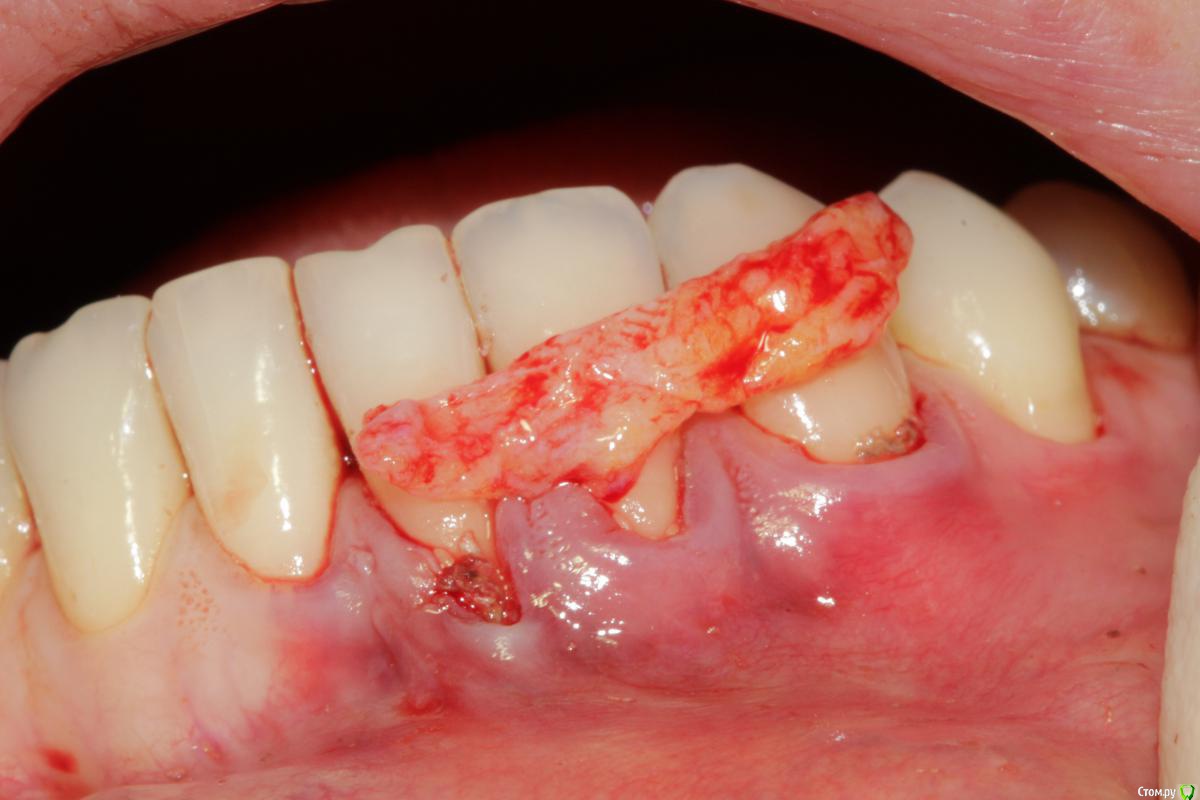

Dc.Petrov Опубликовано 18 сентября, 2015 Поделиться Опубликовано 18 сентября, 2015 Хочу узнать мнение коллег. Можно ли считать результат удовлетворительным? Рассчитывал на лучший итог. 15 Ссылка на комментарий

zzkz Опубликовано 19 сентября, 2015 Поделиться Опубликовано 19 сентября, 2015 через 3-6 мес можно точно сказать, на сегодня все нормуль. 31 еще можно подтянуть. Ссылка на комментарий

Dc.Petrov Опубликовано 21 сентября, 2015 Автор Поделиться Опубликовано 21 сентября, 2015 Почему четверку обошли стороной? Цель изначально была закрыть 31Сейчас уже жалею, что 34 не сделал Ссылка на комментарий

zzkz Опубликовано 22 сентября, 2015 Поделиться Опубликовано 22 сентября, 2015 До ЦЭС у 31 и 34 кажется что можно, по крайней мере по фото Ссылка на комментарий